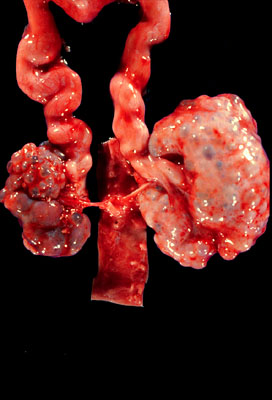

Cystic renal dysplasia

Abnormal fetal organization of renal tissue - gross - The kidneys are small and multicystic, renal components are disorganized. Note the large ureters, urinary tract obstruction early in development is the primary cause of cystic renal.